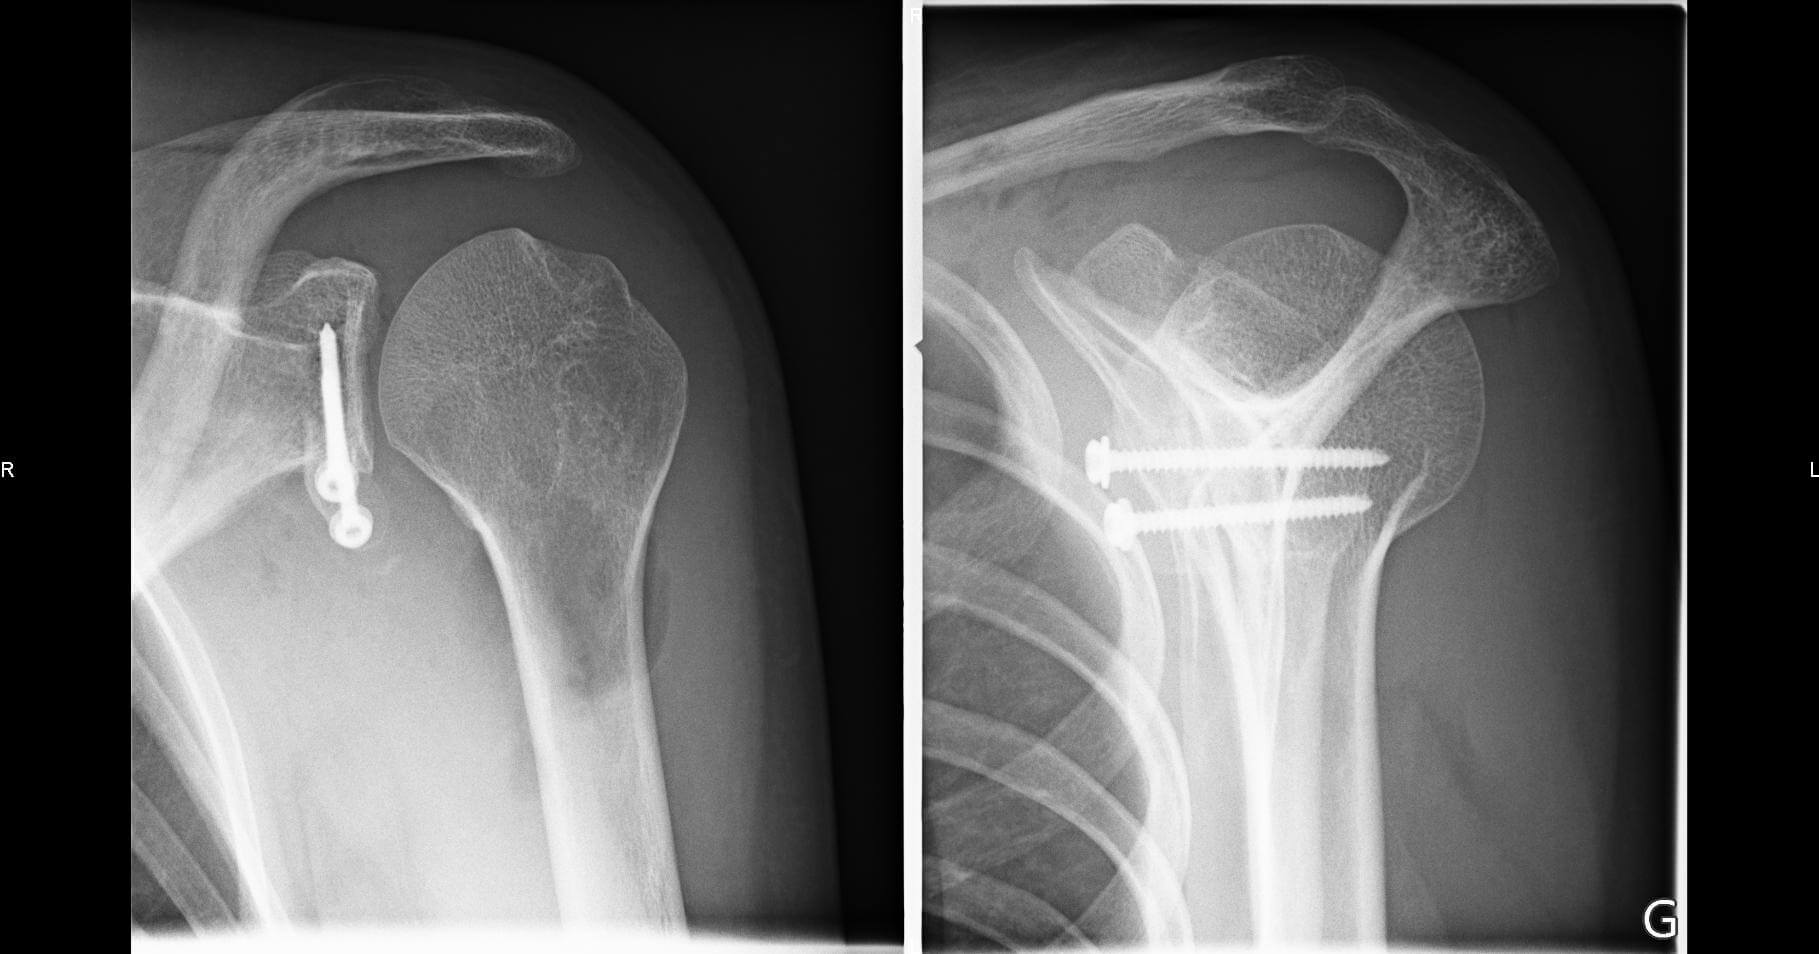

Procedeul Latarjet este o tehnica chirurgicala prin care se incearca recastigarea stabilitatii umarului. Este indicata in luxatiile recidivante de umar, dar uneori aceasta tehnica este folosita ca prima intentie dupa o luxatie acuta scapulo-humerala.

Tehnica chirurgicala consta in sectionarea procesului coracoid si fixarea acestuia in partea anteroinferioara a glenei. Astfel, capul scurt al bicepsului si coracobrahialul actioneaza ca sprijin in zona anteroinferioara a articulatiei atunci cand umarul este in pozitia vulnerabila de abductie si rotatie externa. De asemenea, transferul procesului coracoid printr-o bresa in m. subscapular, face ca insertiile musculare ale celor 2 muschi sa previna partea inferioara a m subscapular sa se deplaseze superior de capul humeral atunci cand umarul este in abductie.

Expunerea colului scapulei este necesara pentru o fixare adecvata a grefei osoase. Printr-o disectie subperiostala se descopera colul scapulei. Este foarte important ca fragmentul coracoid sa fie fixat in jumatatea inferioara a glenei, la maxim 5 mm de marginea articulara.

Se foreaza cu burghiul de 3.2mm o gaura in partea anteroinferioara a colului scapulei care trebuie sa perforeze cortexul posterior si sa nu interfereze cu suprafata articulara. O gaura similara se foreaza in fragmentul coracoid. Este foarte important ca pozitionarea fragmentului sa se faca pe un pat osos sanatos, fara interpozitie de parti moi. Marginile capsulei anterioare se apropie cu suturi separate, inainte de fixarea definitiva a fragmentului osos. Se fixeaza procesul coracoid pe colul scapulei cu un surub maleolar masurat, in prealabil. O saiba poate fi folosita pentru a nu sparge fragmentul osos. Dupa fixarea finala se investigheaza musculocutan pentru a nu fi in tensiune.